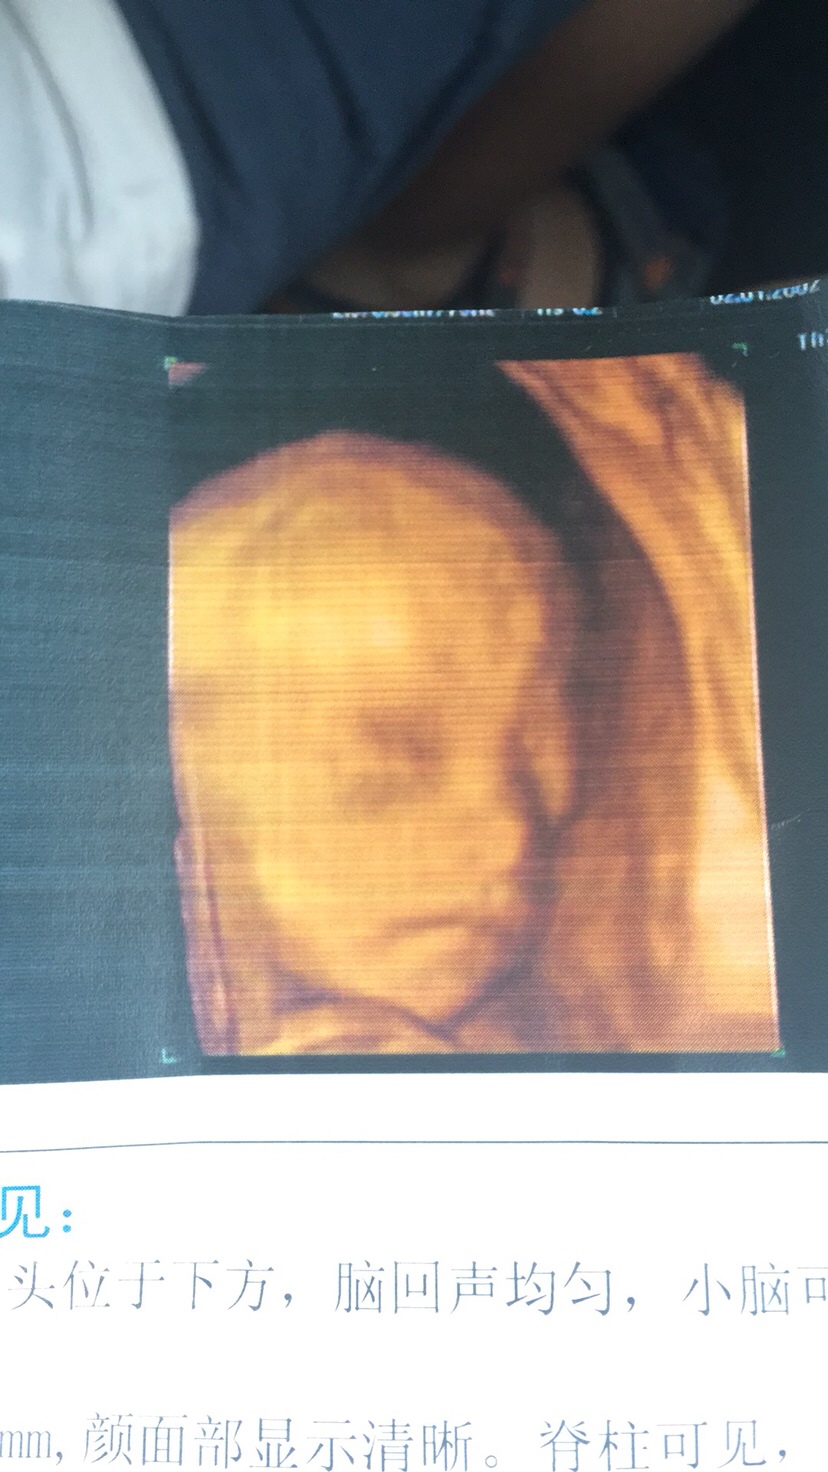

孕24周+4天

接健康女宝宝